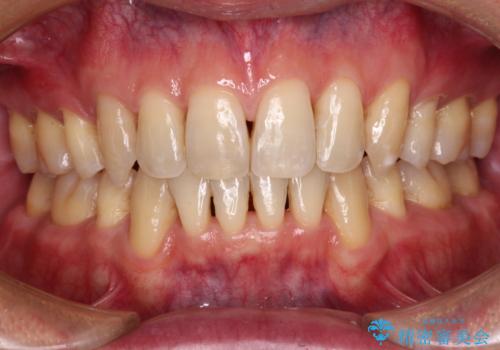

歯肉の腫れた前歯 部分矯正と歯周外科後の審美治療

- 前歯の歯茎に違和感を感じるとのことで来院された患者様です。

左上中央の歯は根の深くまで割れており、抜歯が必要との診断となりました。

それ以外の3歯も歯肉深いところまでクラウンが装着されていたため、歯周外科(歯肉弁根尖側移動術)を行った後にオールセラミッククラウンにて補綴することとしました。

また、下の前歯が隠れてしまうほど上の前歯が下に降りていることを気にされていたため、部分矯正により前歯の位置を事前に改善することとしました。